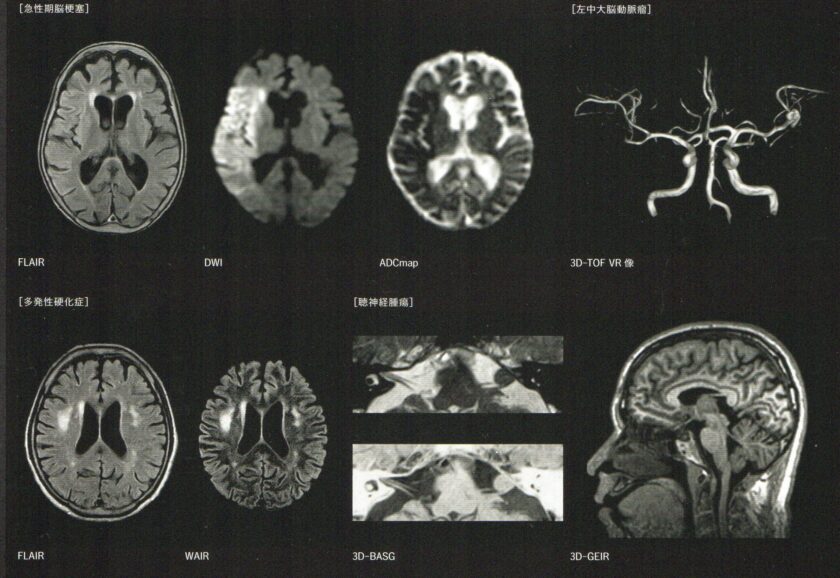

新型MRIを導入しました

富士フィルム製の最新MRI装置を導入しました

3月26日より、新しいMRI装置が稼働しております。より短時間で精密な検査が可能となっております。すぐに画像を見ながら患者さんに説明が可能です。いままで以上に、より正確な診断と治療を提供できるようになりましたので、脳のことがご心配でしたら、お気軽に受診してください。